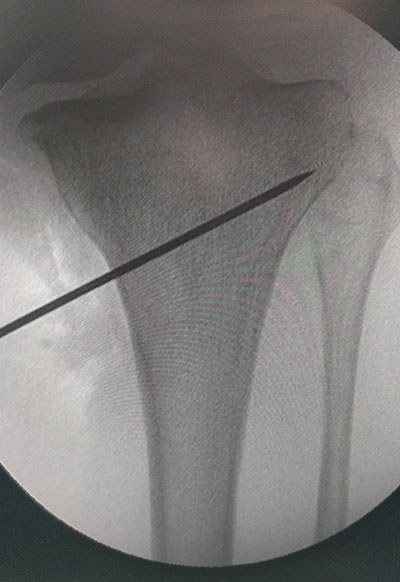

STEPS OF HTO